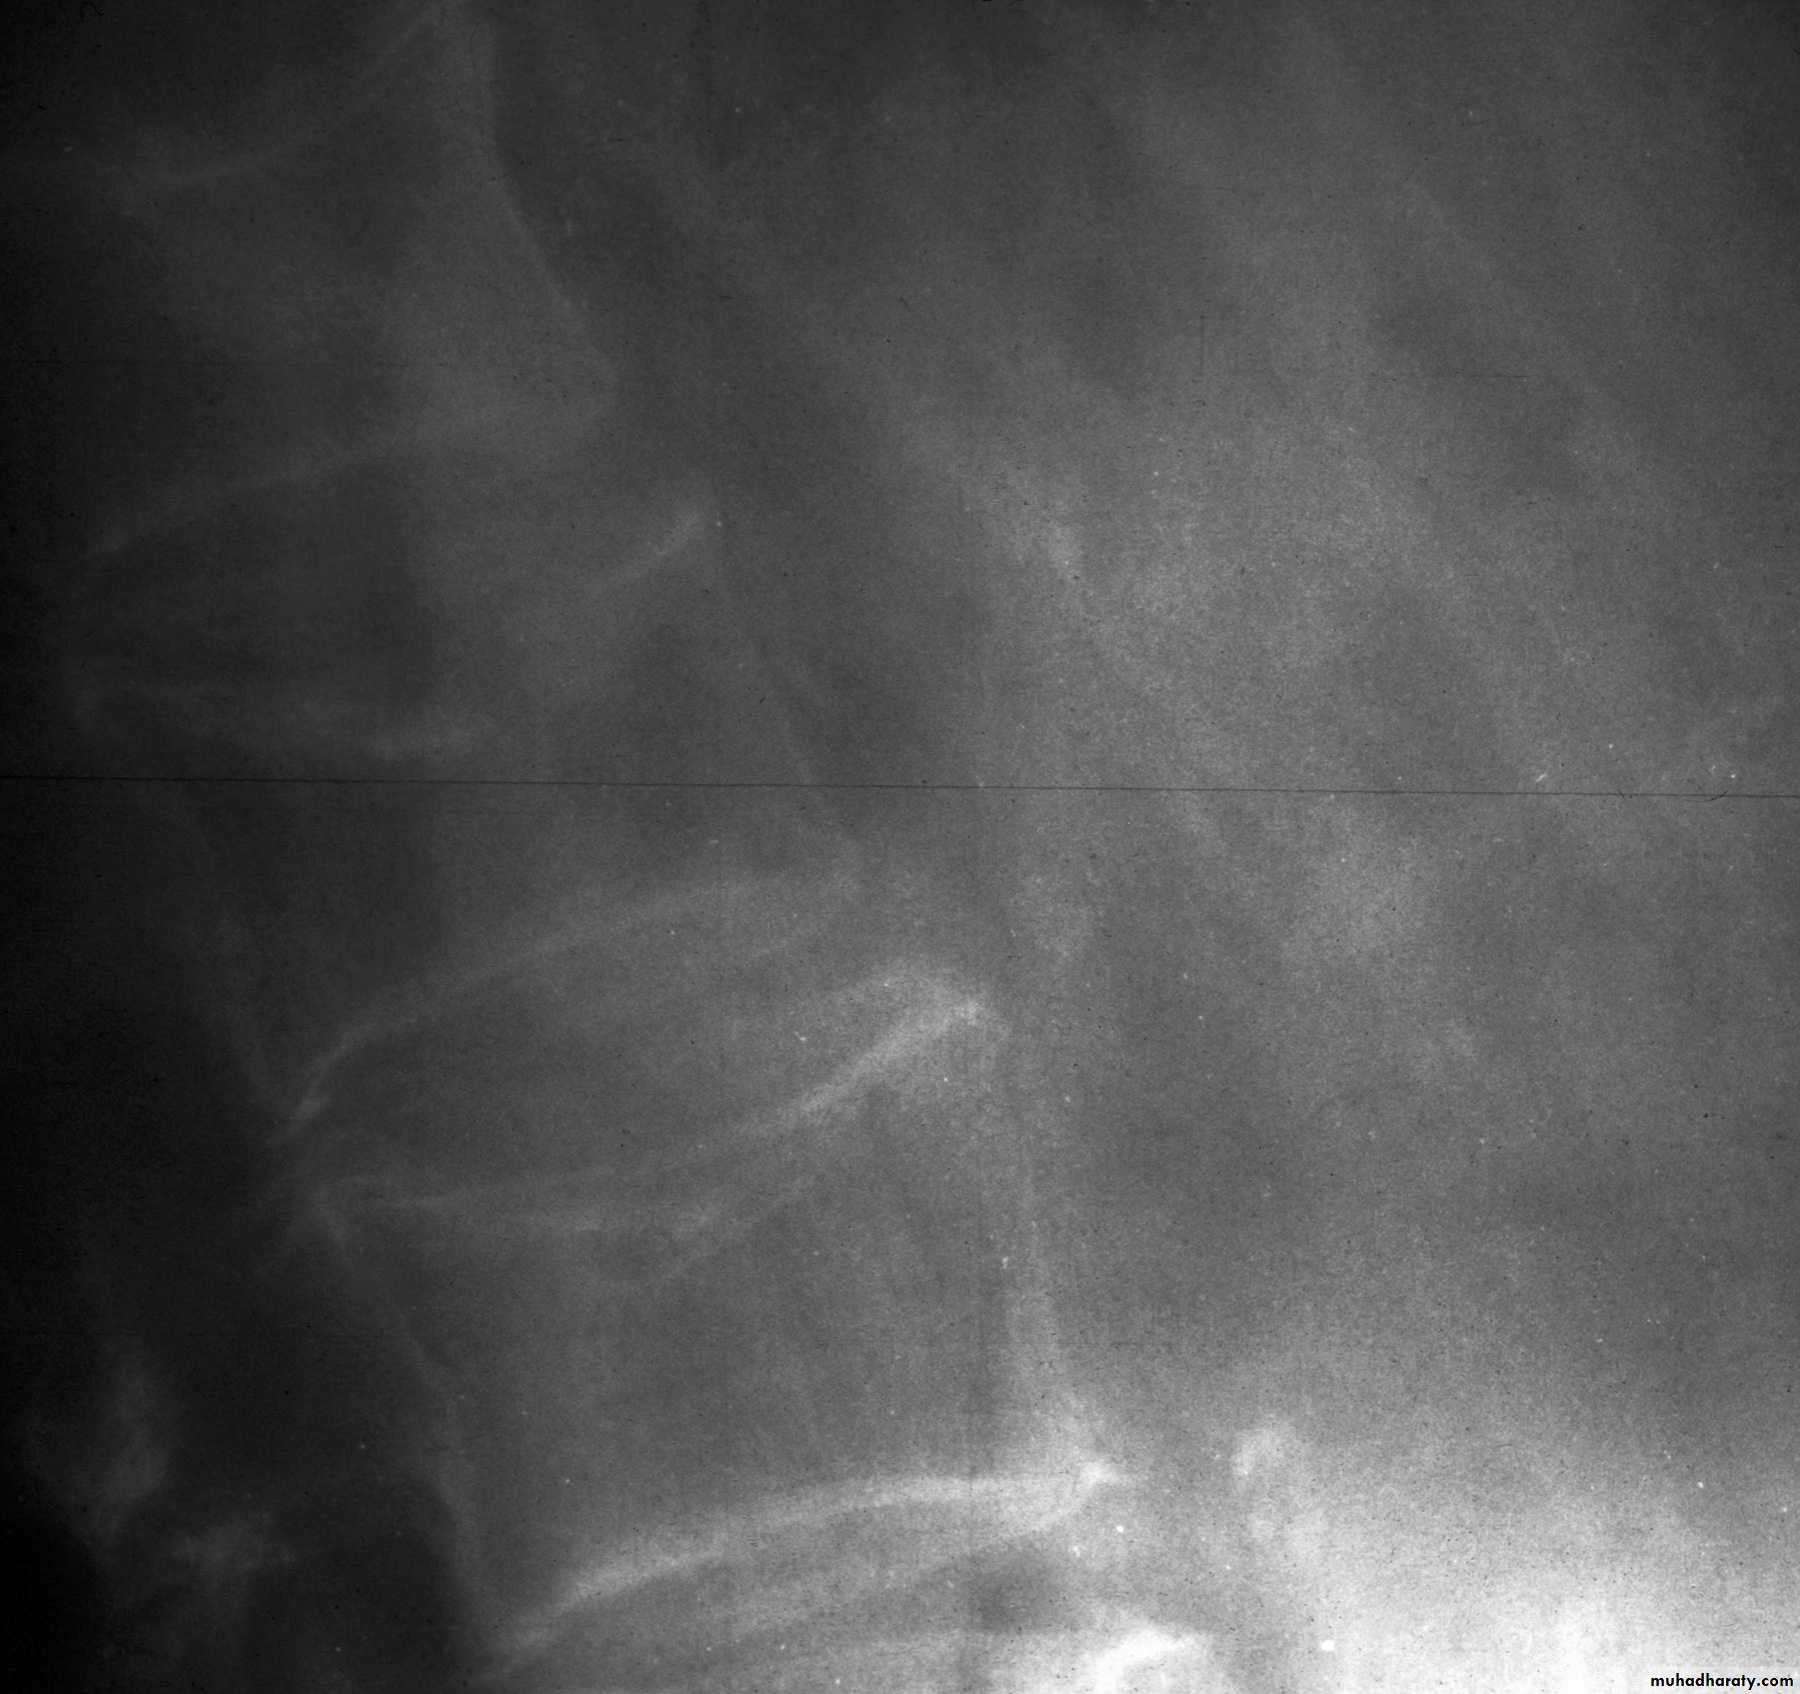

AP view looser’s zone

frogleg view looser’s zone

Osteomalacia: Bone scanRadiographic features

1-Generalized osteopenia2-Looser's zones (pseudofractures):

cortical stress fractures filled with

poorly mineralized osteoid tissue.

* Milkman's syndrome: osteomalacia

with many Looser's zones

Typical location of Looser's zones

(often symmetrical)

Axillary margin of scapula

Inner margin of femoral neck

Rib

Pubic, ischial rami

* Osteomalacia may be indistinguishable from osteoporosis; however, Looser's

zones are a reliable differentiating feature.